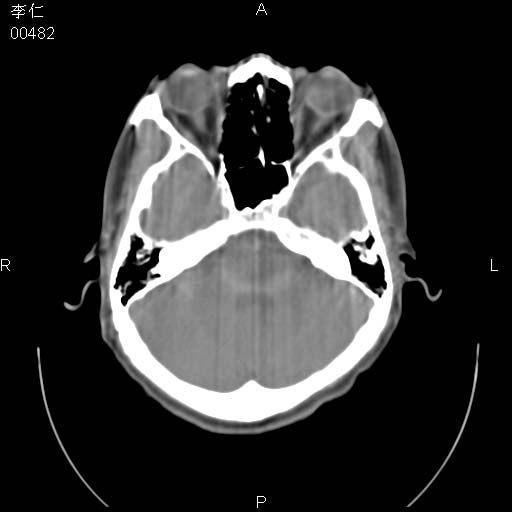

患者男,45岁。于二月前发现左眼稍肿,去看眼科,查肾功(—),来查ct,我看到的是左侧上眼睑内低密度影,ct值是-600到-700hu。

是一个副鼻窦的正常变异,脂肪瘤的密度不可能这么低,-600到-700.

只是空气而已,属正常ct表现。

正常表现,眼睑与结膜zhi间的空气

正常,为结膜囊内气体。

左侧眼球壁光滑,未见异常密度灶,眶内结构清晰,眼内肌、视神经均正常。所见低密度灶,本人考虑:1、五官科翻上睑造成;2、炎症(产气细菌感染)。